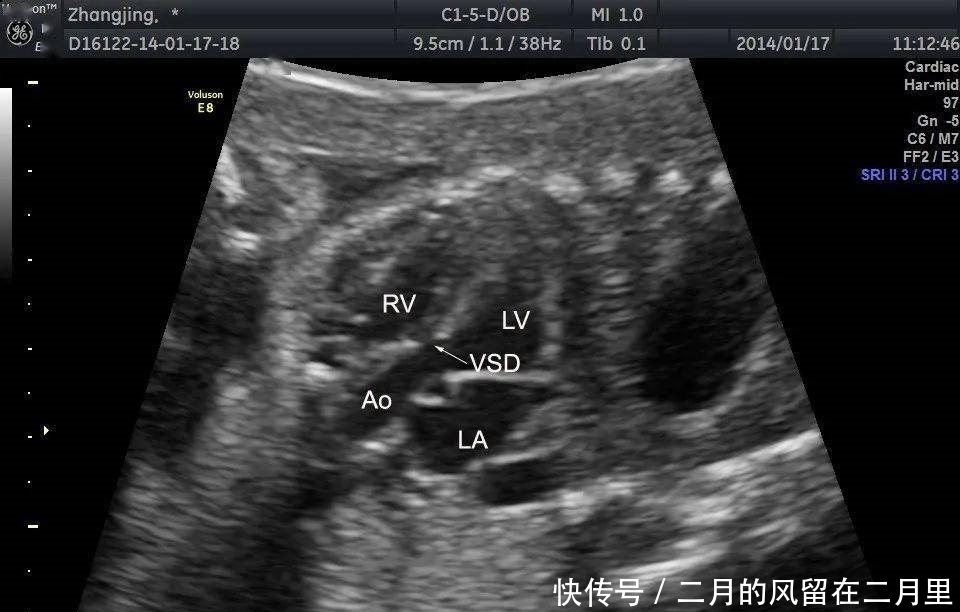

以下是我们掌中宝里几张图,很典型,很清晰。

VSD的超声声像图特征:

(1)室间隔连续性中断,缺损部位断端“回声增强”;

(2)缺损处出现双向分流,CDFI检测可见不同时相红蓝双向的血流